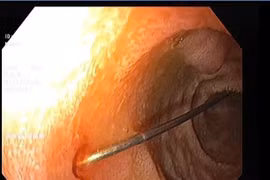

Nội soi đường tiêu hóa không chỉ can thiệp nong rộng lòng thực quản mà còn có thể sinh thiết để loại trừ các nguyên nhân ác tính.

Dịp lễ, Tết, khi người dân ăn uống nhiều, ăn nhanh hoặc chủ quan thường mắc dị vật là xương cá, xương gà hoặc các vật sắc nhọn.

Những dị vật như kim may, ghim, pin cúc áo… có thể gây thủng ống tiêu hóa hoặc xuất huyết. Khi nghi ngờ trẻ nuốt dị vật phải đưa đến cơ sở y tế ngay.